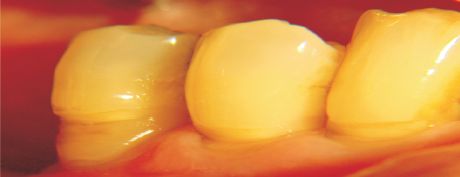

1. Planas o playas, que se ubican generalmente en el 1/3 gingival y avanzan hacia el esmalte coronario (fig. 1).

Fig. 1 Lesion playa, más amplia que profunda.

Asociada clásicamente a erosión